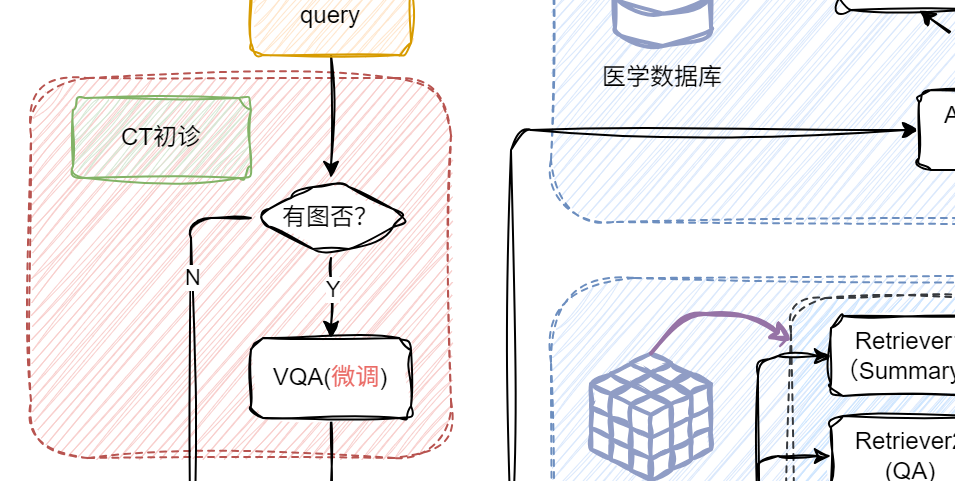

首先登场的是

当用户提问中包含图片时,系统会自动触发 VQA,对图像进行结构化信息提取,挖掘上下文关键内容;若没有图像,就跳过这步,直接进入文本处理环节,效率UPUP!

🗝️原理:输入(用户带CT提问+微调后的VQA的初诊结果) → 向量检索相关医学知识 → 与输入拼接 → 喂给模型生成回答。